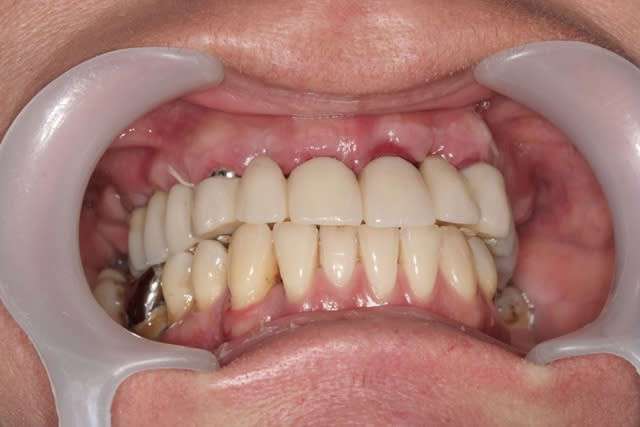

revenons en plutôt au sujet: une MCI, une patiente, et voilà la cicat à 3jours car je viens de la revoir avant ma semaine de congés (pas de pb, s'il y a quoi que ce soit elle a mon n° de portable...)

j'ai remis la photo juste post chir que vous jugiez vous même du repositionnement de la gencive qui est en train de se faire...;-)

je pense que çà va être bien joli pour le définitif...;-)